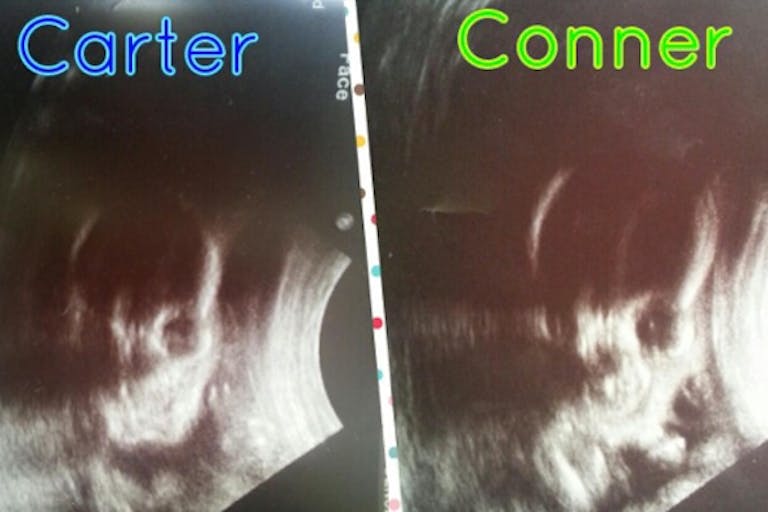

Then they got the unexpected news: their twin boys were actually conjoined twins. First Cost News has full coverage with some highlights we have pulled out below:

The couple’s boys, which they intend to name Carter and Conner, are connected facing each other from their sternums to their upper waist lines.